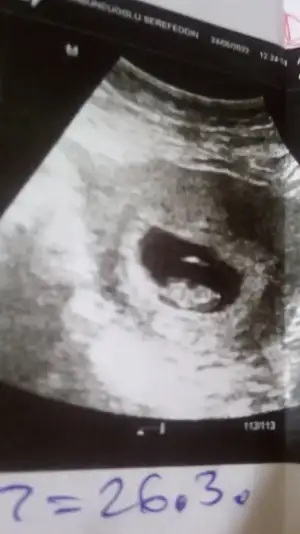

Merhaba bana da söyleyebilir misiniz :) 7+2 karınndan

paşa gibihala bir tahminde bulunmamış olamaz doktorunuz?